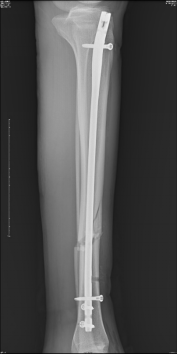

初步复位完成后,CO接骨机器人牵引下置入髓内钉

术后影像资料